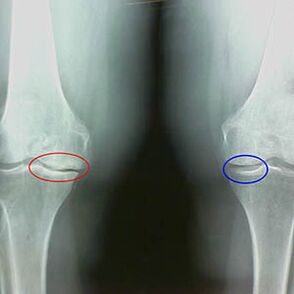

Vroege X -Ray -kenmerken van de tweede fase van knieartrose:

- de puntige randen van de interbeschrijving knobbeltjes op het scheenbeen, waar het kruisvormige ligament is bevestigd;

- het beperken van de gezamenlijke kloof aan de mediale zijde;

- De puntige randen van de condyles van botten aan de mediale zijden, minder vaak in laterale - afhankelijk van de ontwikkeling van de valgus of varieurgewrichtsvervorming.

Voor de tweede fase in Larsen Het vernauwing van de gezamenlijke kloof met meer dan 50% is kenmerkend, maar dit kan alleen worden gecontroleerd in dynamiek of vergelijking met een in tegenstelling tot een gewricht.

De röntgenfoto toont de aanwezigheid van osteofyten, een verandering in de ruimte tussen de dijbeen- en tibia -botten, die het verlies van kraakbeen in de knie aangeeft. Soms vertoont de X -Ray van de kniegewrichten significante tekenen van kraakbeenkleding, maar patiënten ervaren geen significante pijn.Integendeel, artrose van de eerste fase kan de functie van de knie verstoren, omdat de oorzaak van pijn hypotonische spieren is.